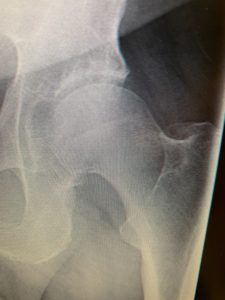

Above is the hip in question – compared to my almost perfect Left Hip pictured below. My Dr. asked how I’m even able to walk right now……